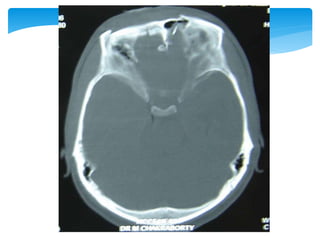

 Between the dura mater and arachnoid membrane

 Tearing of bridging veins

 Severe brain damage more likely than with epidural

haematomas

 Approximately 60%, but can be lowered with rapid surgical

intervention and aggressive medical management

Subdural Haematomas